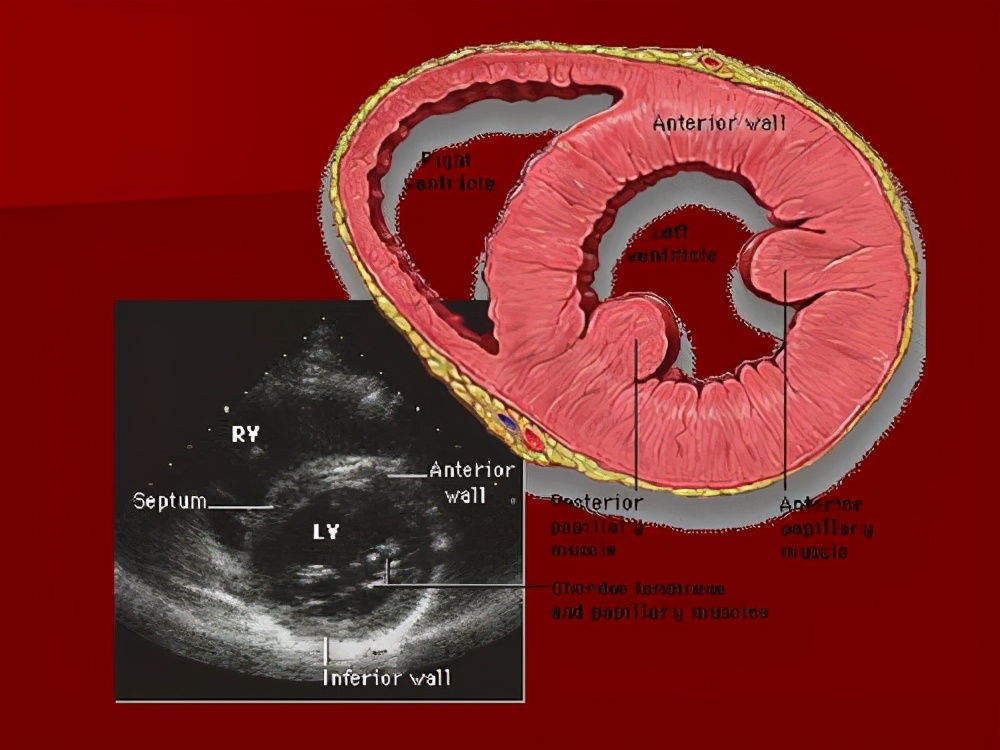

(2)超声心动图

心包增厚、钙化明显,心室体积可减小、心房增大,尤其左心房增大。室壁增厚,活动消失。收缩期室间隔活动减少,舒张期则异常反向活动。少量局限性心包积液时有发生。